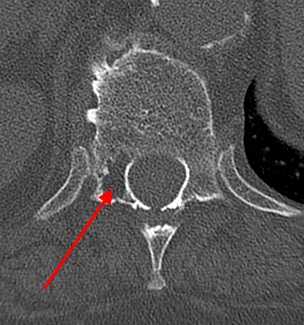

При КТ определяется участок в теле позвонка, в его дуге, ножках или суставных отростках, чаще всего имеющий форму шара или эллипсоида, или неправильную форму. Размеры гемангиомы различные - на томограммах можно можно опухоль начиная от 0,5 см. Редко встречаются гигантские сосудистые образования, занимающие практически весь объем позвонка. Рентгеновская плотность данного участка снижена по сравнению с плотностью губчатого вещества и, тем более, замыкательных пластинок.

На изображении представлен поперечный срез через позвонок. В теле позвонка - типичная гемангиома (H). Цифрой 1 отмечены утолщенные и разреженные трабекулы губчатого вещества, цифрой 2 - периваскулярные пространства, сосудистые лакуны. При компьютерной томографии они имеют низкую плотность, приближающуюся к плотности жира (гемангиолипома).

Типичная гемангиома в грудном позвонке. На аксиальном срезе - справа - отчетливо виден характерный «точечный» «рисунок», обусловленный утолщением трабекул и большим количеством периваскулярного жира.

Небольшая сосудистая опухоль в боковых отделах тела первого поясничного позвонка. При компьютерной томографии выявлен гиподенсный участок плотностью -25…-30 единиц Хаунсфилда, с типичными утолщенными и «разреженными» трабекулами губчатого вещества.

В зависимости от количества периваскулярного жира плотность гемангиомы может колебаться от +200 единиц Хаунсфилда до -40 и меньше, но практически никогда не достигает плотности жировой ткани (-100 единиц Хаунсфилда). В структуре опухоли видны множественные разреженные и утолщенные до 1-3 мм трабекулы, дающие характерный «мелкоточечный» рисунок на аксиальных срезах и «полосатый» рисунок на аксиальных и корональных изображениях. После введения контрастного вещества строма опухоли может усиливаться, зачастую весьма значительно. Наибольшую плотность сосудистые опухоли имеют в артериальную фазу контрастирования. Контраст из сосудистых лакун вымывается быстро, поэтому уже в венозную фазу плотность образования существенно снижается.

1) Распространение опухоли на задние отделы позвонка - дужку, поперечные и суставные отростки, остистый отросток.

2) Распространение опухоли на поперечно-реберный сустав и на проксимальные (начальные) отделы ребра с типичным ангиоматозным изменением его структуры.

3) Появление локального или диффузного вздутия тела позвонка, нарушение его обычной формы.